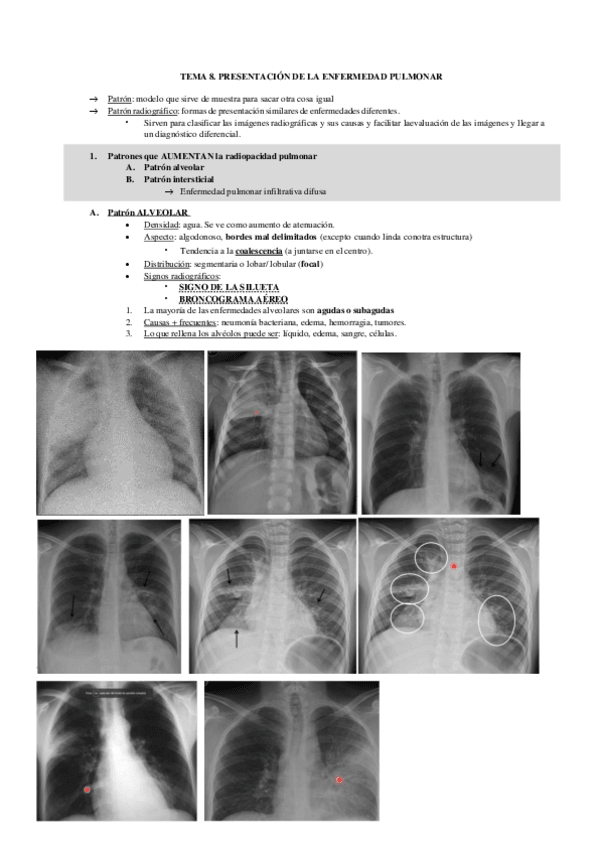

TEMA-8.pdf

Teneis todos los temas del primer parcial (1-16). Del segundo parcial teneis 17-18-19 (os faltarian 20-24). Mi recomendación es que os estudies las radiografias de memoria porque son las que os entran en el examen.

Tema-8-Torax-2.pdf

Tema-8-enf.pdf